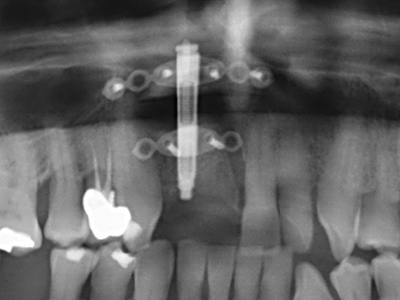

Fig. 1: Preparación de una tapa ósea conforme con Piezomed (W&H, Salzburgo, Austria)

Fig. 2: Defecto del maxilar superior lateral vertical y horizontal con línea de la sonrisa alta, con indicación para la reconstrucción antes del implante.

Fig. 11: El ortopantomograma posoperatorio presenta el aumento vertical y la elevación del suelo del seno.

Fig. 12: Después de seis meses de cicatrización se muestra una cresta maxilar vital con unas dimensiones suficientes en todas las direcciones.